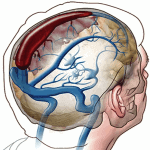

Hộp sọ được chia ra thành những khoang nhờ các nếp gấp màng cứng (dural reflections) của liềm não (falx cerebri) và lều tiểu não (tentorium cerebelli): lều tiểu não tạo thành hố đại não và hố sau, liềm não tạo nên khoang bán cầu đại não phải và trái. Tăng áp lực nội sọ thường dẫn tới thay đổi chêch áp giữa các khoang và dịch chuyển các cấu trúc não. Thoát vị não là sự dịch chuyển cơ học của não, dịch não tủy và mạch máu lớn của não từ khoang này sang khoang khác trong hộp sọ…